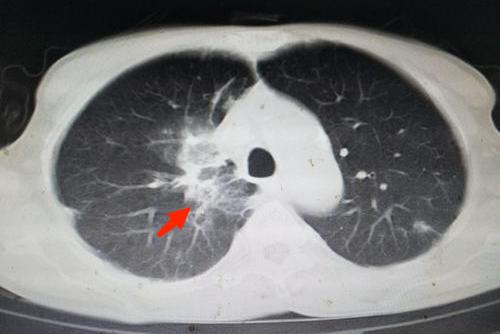

CT表现

肺脓肿胸部CT扫描较普通的胸部平片检出率高,CT检查可发现多发类圆形的厚壁脓腔,脓腔内有液平面出现。脓腔内壁常表现为不规则状,周围可有模糊炎性阴影。